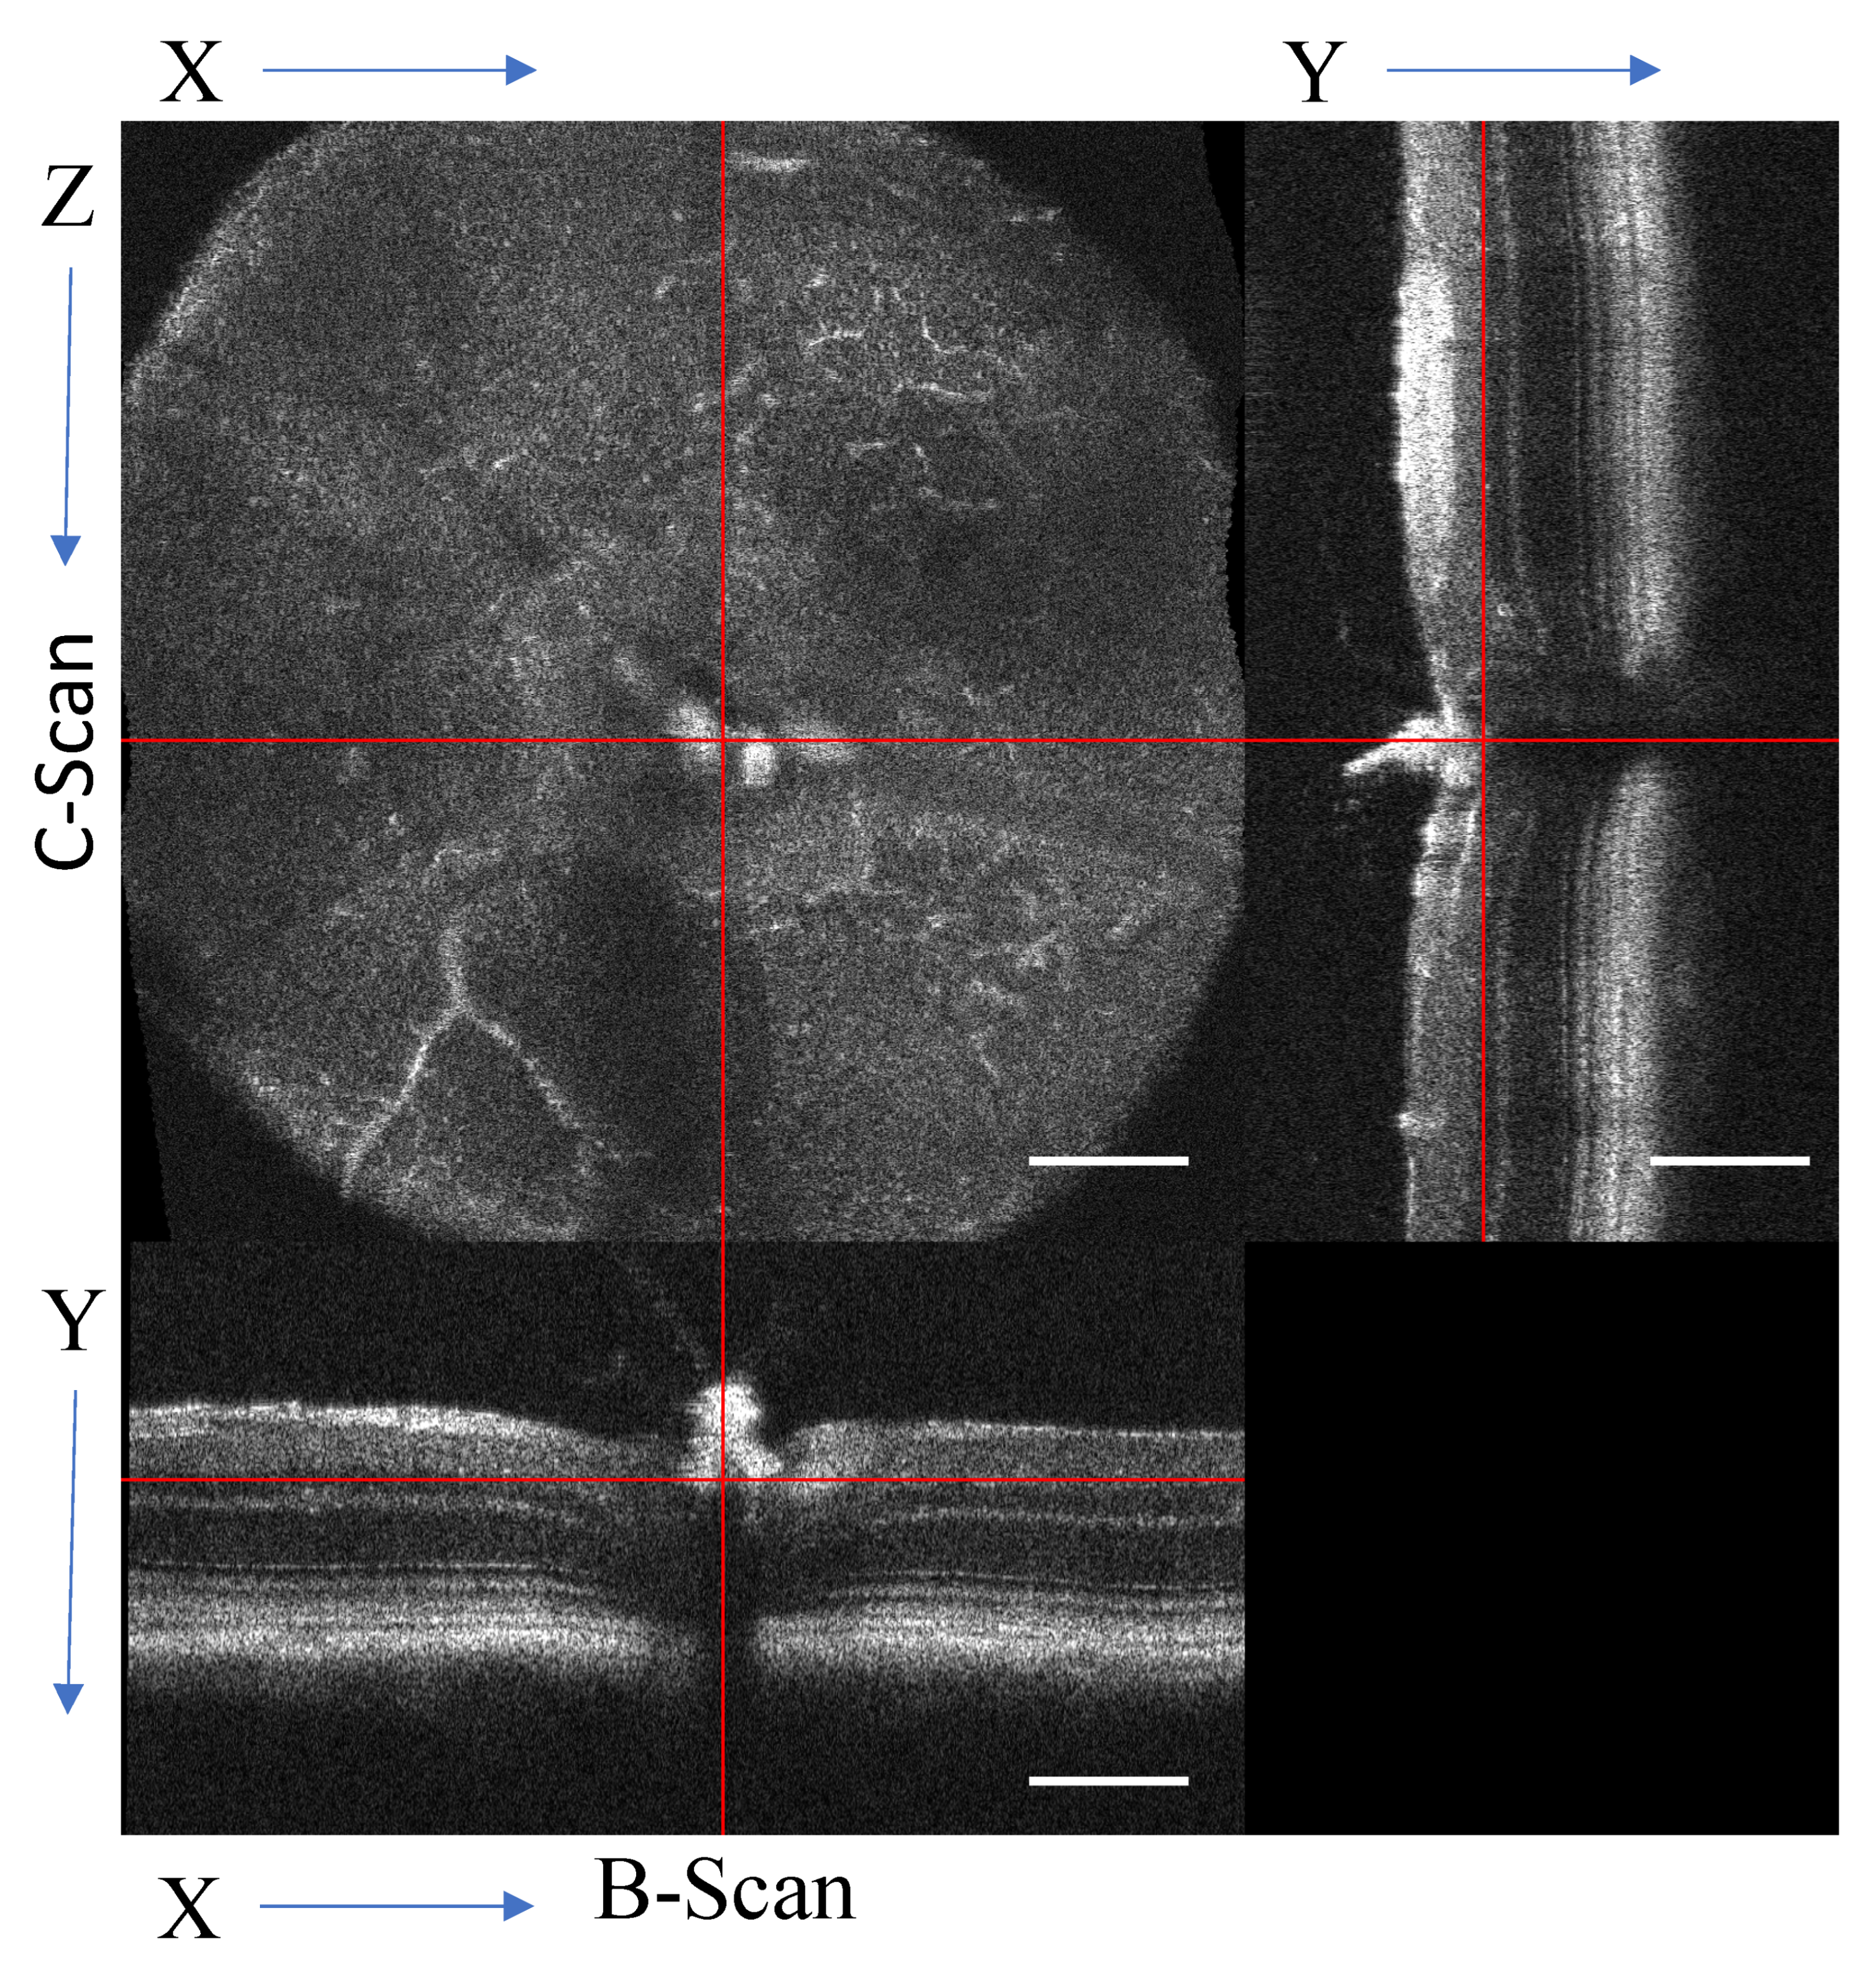

3.7. Volumetric Analysis and High-Resolution B-Scans